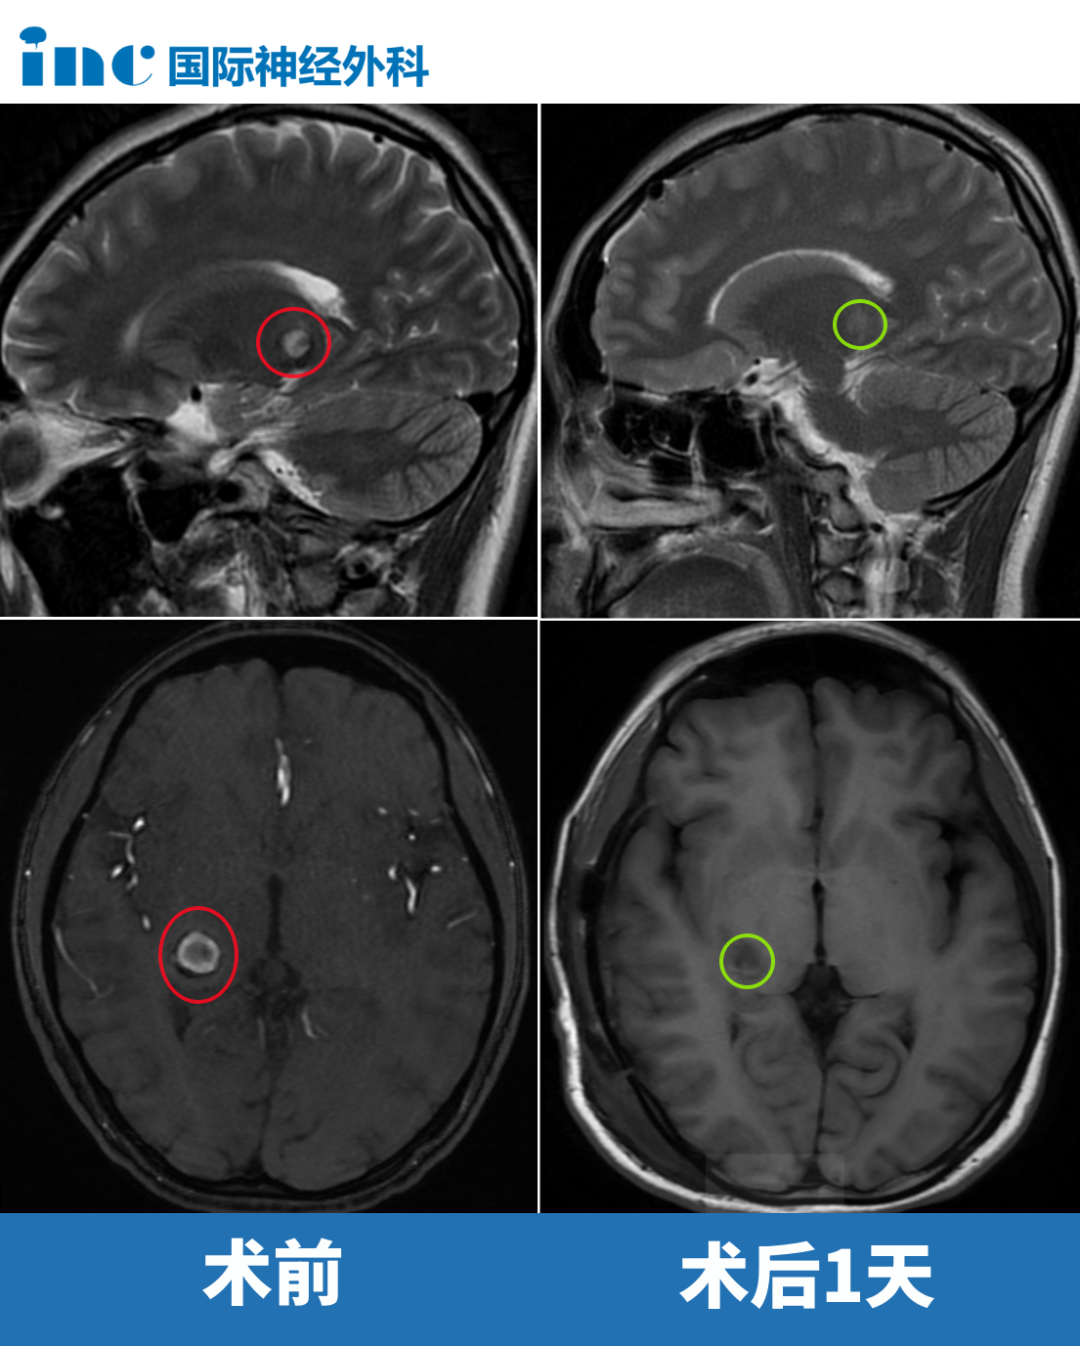

这位左侧丘脑占位患儿肿瘤呈弥漫性生长,已侵入脑实质。手术过程中任何细微偏差都可能引发严重后果。在巴教授主刀下,手术当天患儿即转入普通病房,神经功能检查显示握拳、抬腿等动作正常。

点击阅读:10岁男孩开颅术后竟无需进ICU——这个位置0.1毫米失误都不可以!